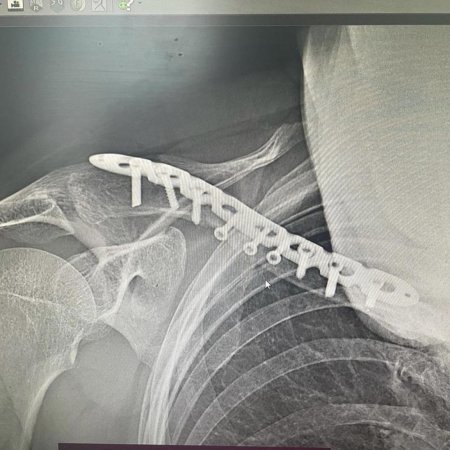

Рентгеновский эффект создает фантастические композиции в этих фотографиях девушки, чье тело становится прозрачным, демонстрируя скелет и внутренние органы. Она позирует в разных позах, ее силуэт светится загадочным свечением. Каждый кадр передает атмосферу научной фантастики и медицинского искусства. Ее кожа кажется полупрозрачной, позволяя увидеть кости и мышцы. Фотографии рассказывают о хрупкости человеческого тела и его внутренней красоте. Девушка то стоит в задумчивости, то делает грациозное движение. Эти иллюстрации вдохновляют на размышления о человеческой анатомии и уязвимости. Каждая картинка - это момент прозрения, когда внешнее уступает место внутреннему. Девушка воплощает образ современной Медузы, сочетающей красоту и загадочность.